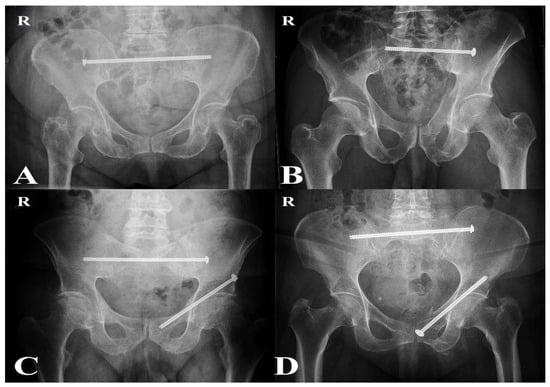

Interests: orthopedic trauma; fragility fractures; biomechanics; hip surgery; bone defect; nonunions; pelvic ring; acetabular fractures

Orthopaedic trauma care has undergone major advances in recent years, particularly in the management of fragility fractures, complex pelvic and acetabular injuries, postraumatic bone defects, and amputations. Meanwhile, deeper understanding of biomechanics, biology, and implant charachteristics has led to more individualized treatment approaches.

- pelvic ring

- acetabular fractures